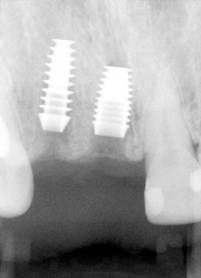

A 43 year-old lady has lost #7 and 8 due to caries for ~ 2 year. It appears that the ridge is wide (Fig.1). To place implants in ideal position, cone beam CT is planned. Models are mounted (Fig.2); diagnostic wax-up is finished (Fig.3). Drill sleeves (arrowheads in Fig.4; 10 mm long, 2.2 mm in diameter; Straumann) are placed lingual to the incisal (I) edges of the neighboring teeth. The position of drill sleeves is confirmed by CT: between the incisal edge and the cingulum (Fig.5). The cross sections at #7, 8 and 9 are shown in Fig. 6, 7 and 8, respectively. However, the long axis of the sleeve (S) or the natural tooth #9 is not aligned with that of the alveolar ridge. This orientation is good from prosthetic viewpoint, but we cannot place a long or wide implant. The lateral view of the three-dimensional image shows that the long axis of the crown (C) of #9 is not in line with that of its root/ridge (R, Fig.9). It appears that the trajectory of an implant should be not decided by wax-up, but should be adjusted to accommodate the morphology of the alveolar ridge. In all, the drill sleeve (S) should be moved and tilted more labially to place the longest and largest implant.

Back to model surgery (Fig. 10, upper panel), the osteotomy for #8 (pin from Straumann) has been adjusted parallel to the surface of the alveolar ridge (R), as compared to that of #7 of the previous design. Next, the incisal end of #7 and 8 pins is labial to the incisal edge, instead of lingual to the latter (Fig.11, lower panel). Finally the drill sleeves are positioned labial to the incisal edge (Fig.12). The labial view also shows the point (Fig.13). In addition, the model surgery allows the surgeon to experience the perforation of the labial bone (apical fenestration defect, single arrowhead and large dehiscence defect, double arrowheads) before a big day.

The adjusted stent fits well after raising the flap (Fig.14). Initial osteotomy is made using the stent. The osteotomy for #8 is located in the middle of the ridge labiolingually, whereas that for #7 is too lingual. Adjustment is made freehand. The final osteotomy is shown in Fig.15: 4.0 mm in diameter for #7 and 4.5 mm for #8. With direct vision (large exposure) and digital palpation, there is no perforation (not shown). There is concavity in the labial plate (arrowheads in Fig.15), which is corrected by connective tissue graft. The arrowhead in Fig.16 points to the suture that stabilizes the graft against the labial mucoperiosteal flap.